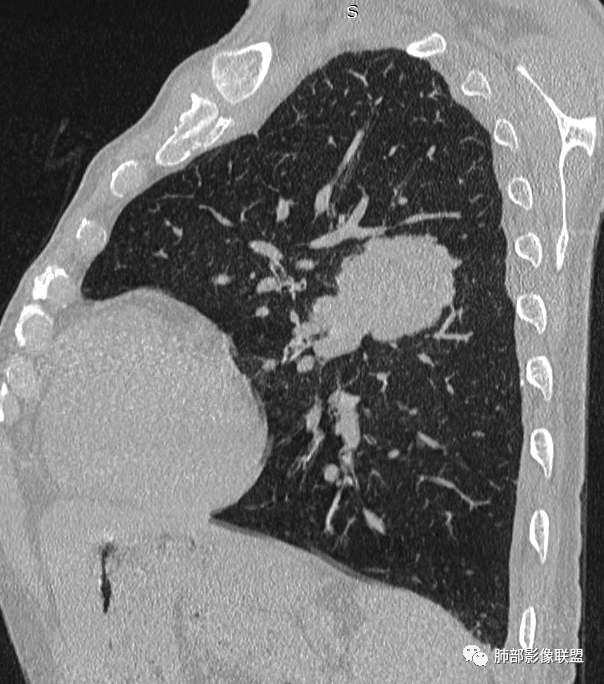

左肺上叶大肿块,膨胀性生长,边界清,密度较低,见部分坏死区,强化弱,肿块见支气管充气V扩张征,分布僵直,枯树枝特点,另一个重要特点血管造影征,淋巴瘤,肿块长轴与胸膜平行,与隐球菌鉴别,隐球荚膜抗原检查,明确诊断经皮肺穿刺。另胸膜钙化(问诊既往有无患胸膜炎病史)。

左肺上叶胸膜下肿块,宽基底与胸膜相连,跨叶裂,边缘清晰膨隆,其内支气管充气,部分扩张、僵直,无明显强化,血管造影征,考虑淋巴瘤,鉴别腺癌

左肺胸膜下巨大占位,跨叶裂,宽基底与胸膜相连,胸膜钙化,平扫密度较低,强化不明显,可见内部血管显影,支气管充气征和扩张,考虑为恶性,倾向于淋巴瘤

左侧胸腔巨大肿块,跨叶生长,临近胸膜钙化,边缘模糊,可见支气管影,定位肺内,增强后轻度强化,边缘见血管影,考虑淋巴瘤,鉴别肉瘤

左肺上叶胸膜下肿块,膨胀性生长,边界清晰,密度不均部分坏死,未见强化,病灶内支气管迂曲扩张,病灶长轴与胸膜平行,胸膜下脂肪间隙存在,胸膜钙化,考虑放线菌?毛霉?鉴别淋巴瘤

支持淋巴瘤,左上肺大肿块,有分叶,边缘光整,病灶内密度不均,可见支气管扩张征,增强后可见血管影征。周围肺野清晰。

左肺上叶肿块,宽基底与胸膜相连,跨叶裂,边缘清晰膨隆,可见小分叶,其内支气管充气,部分扩张、僵直,呈枯枝征,支气管达边征,增强无明显强化,可见血管造影征,考虑恶性病变,淋巴瘤,鉴别粘液腺癌。

我再建一下血管。支气管进入,但是近端推移,堵塞

大肿块,边缘光滑,深分叶

近端支气管堵塞、推移为主

部分类似于脐凹征

内部支气管扩张

肺动脉推移为主,边缘部分进入

大肿块、表面光滑但深分叶,肺门侧支气管堵塞

回头看,内部支气管近端其实不连续,伴随肺动脉不存在

这两点就不符合

1)部位:周围型或中央型软组织肿块,以周围型为多见,且肿瘤多位于肺上叶。如本例:该肿瘤位于左肺上叶。

2)大小及形态:由于本病恶性程度高,早期症状不明显,发现时肿块均较大。如本例病变巨大。

3)肿块边界和边缘:多较清楚,呈圆形、类圆形,且由于肿块生长速度不均匀,可见分叶,毛刺少见。有报道肿块周围毛玻璃影是多形性癌特征表现。

4)密度:肿块平扫为软组织密度,由于体积较大,内部常见大片状坏死,可出现不规则厚壁空洞或坏死内多发无壁小空洞,坏死多不均匀:坏死灶内可见如柳絮样的斑片样强化灶,坏死边缘与非坏死区分界不清本例坏死较明显,密度不均匀。

5)肿瘤强化方式:肺部恶性肿瘤强化程度与其血供丰富程度相关,血供丰富多强化明显,反之则较差。由于PSC 周边实性部分富血供及内部黏液变性、坏死,增强后肿块多数呈轻-中度边缘环形强化或不均匀小斑片状强化。国外学者对照病理发现肿瘤细胞或胶原组织增强扫描时强化,无强化的低密度区代表了黏液样变性区和出血坏死区。